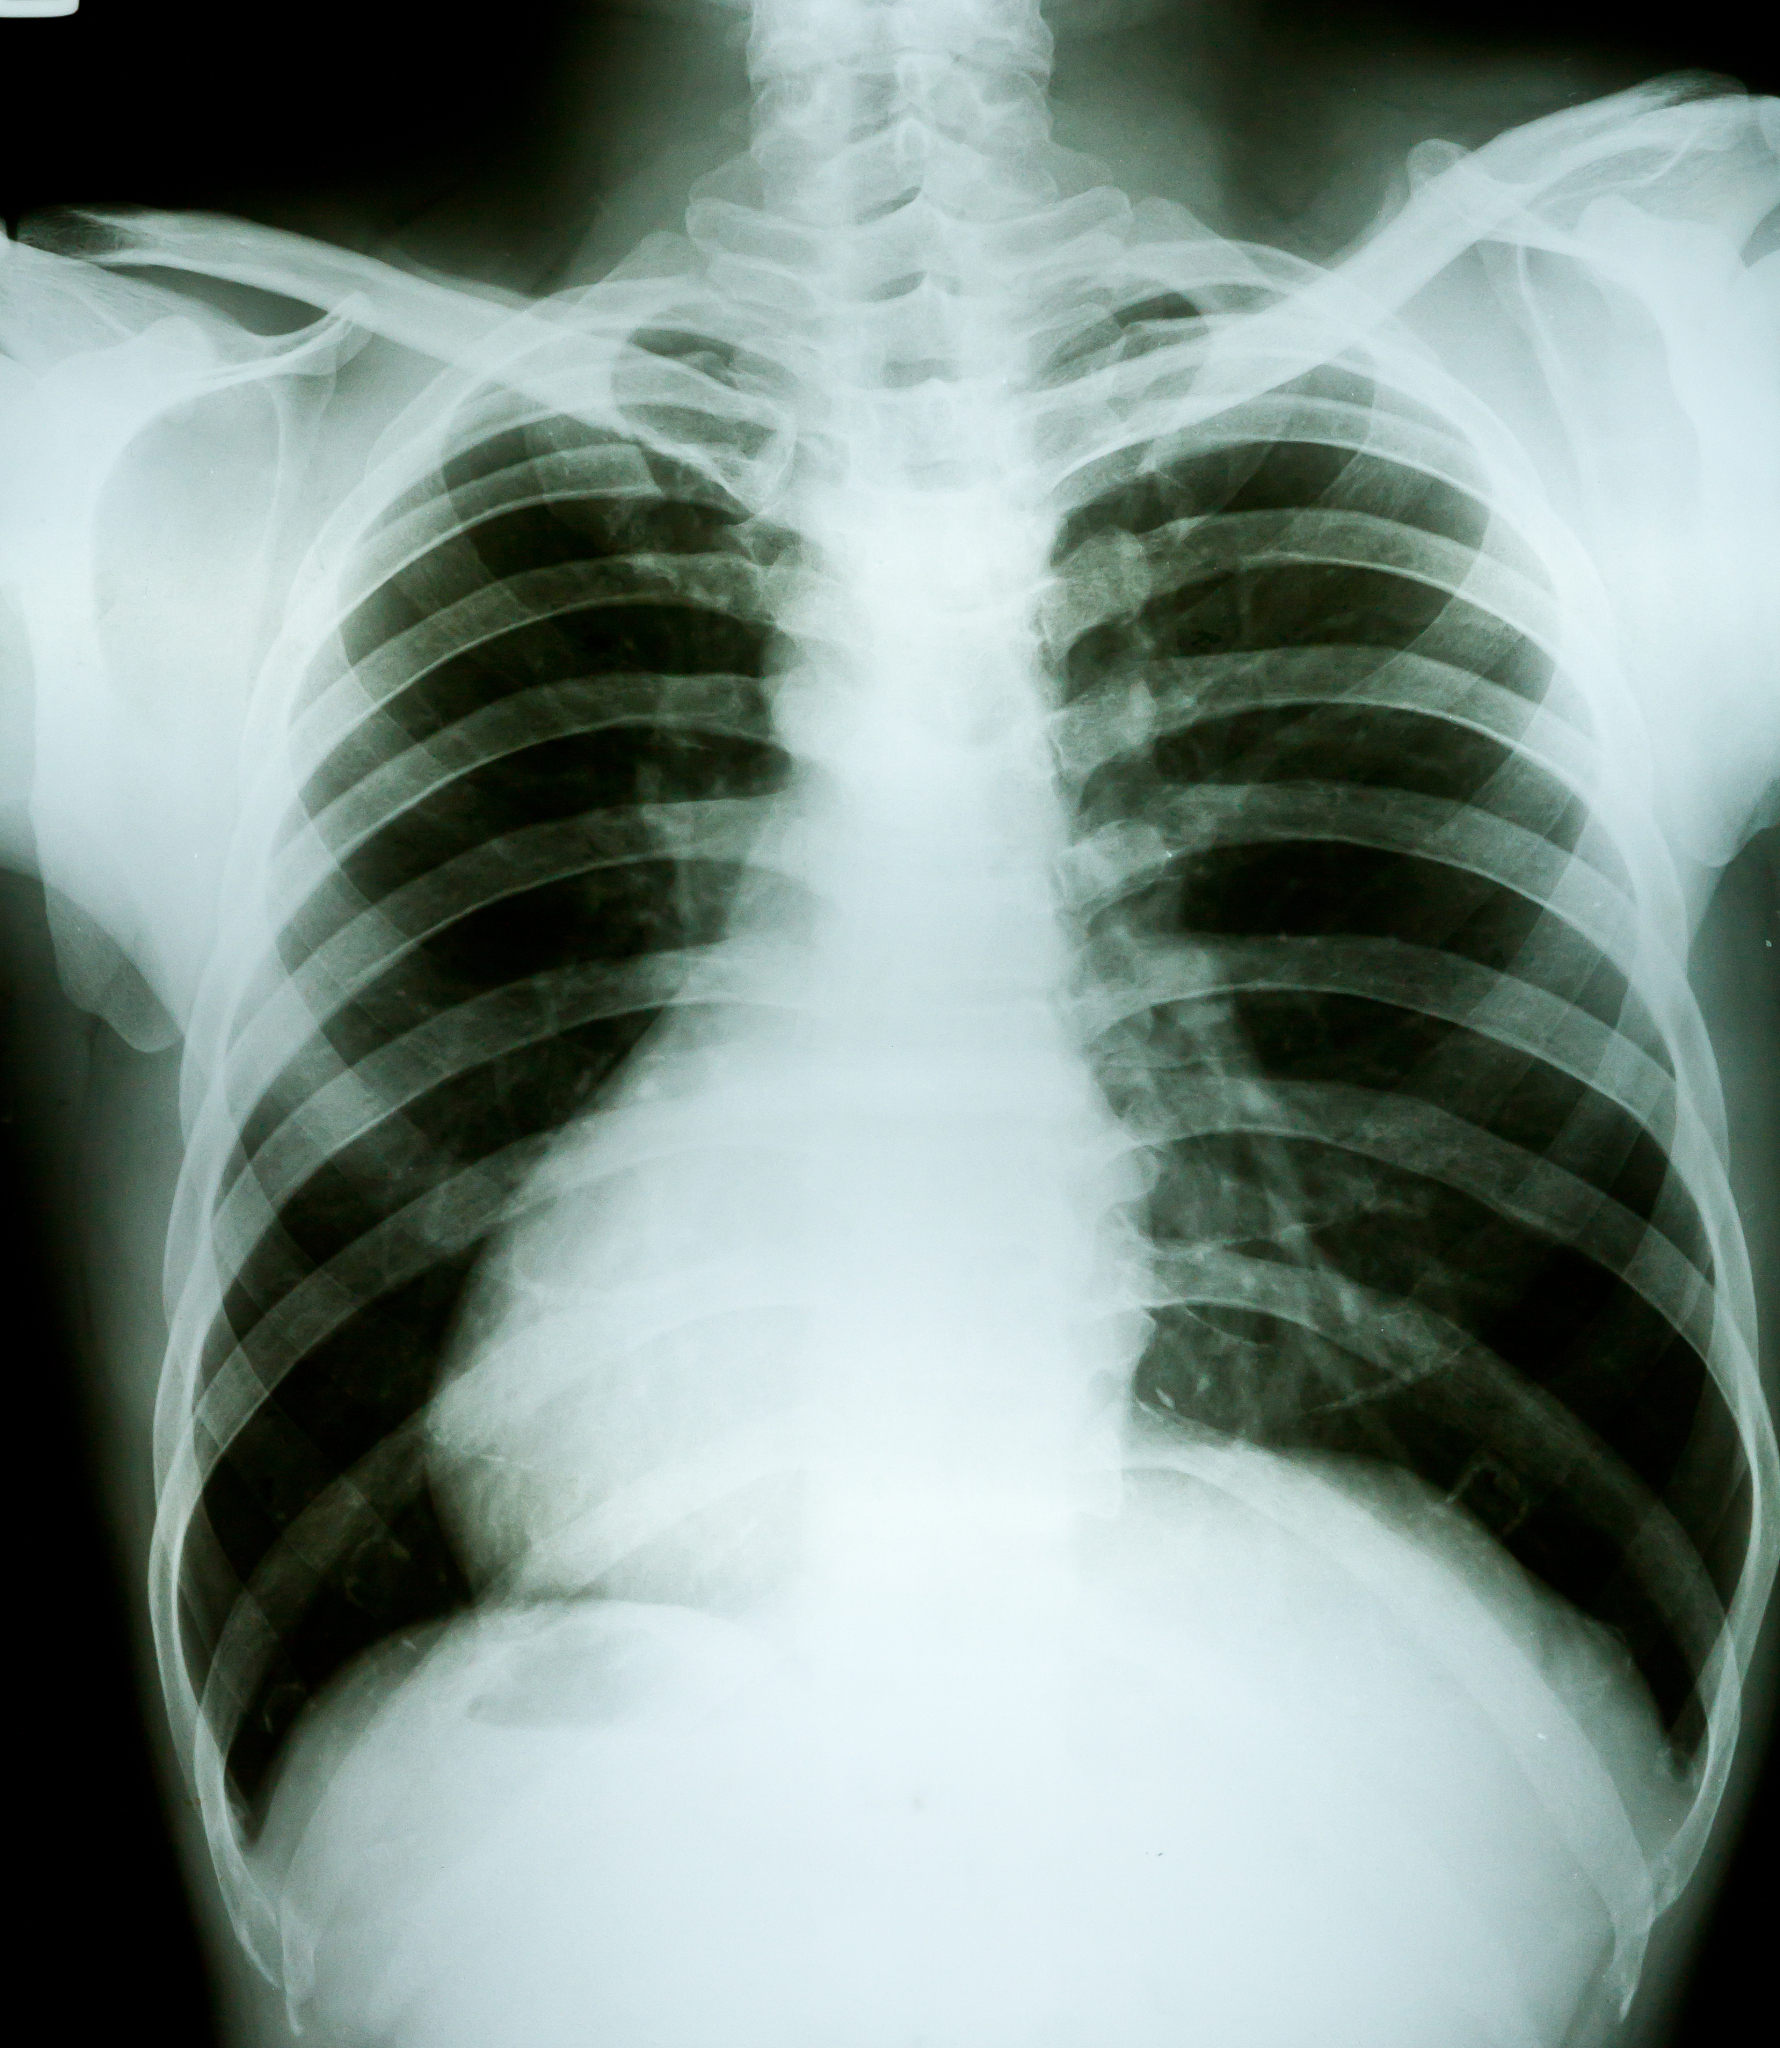

在我参与的科研项目中,我们对老年慢性阻塞性肺疾病(COPD)患者的肺部信息需求现状进行了调查研究。通过该研究,我深刻认识到疾病管理需要患者积极参与和主动管理。因此,我开始关注患者自我管理方面的研究,并思考如何有效地提高患者的自我管理能力。

老年慢性阻塞性肺疾病患者肺部信息需求调查及影响因素分析